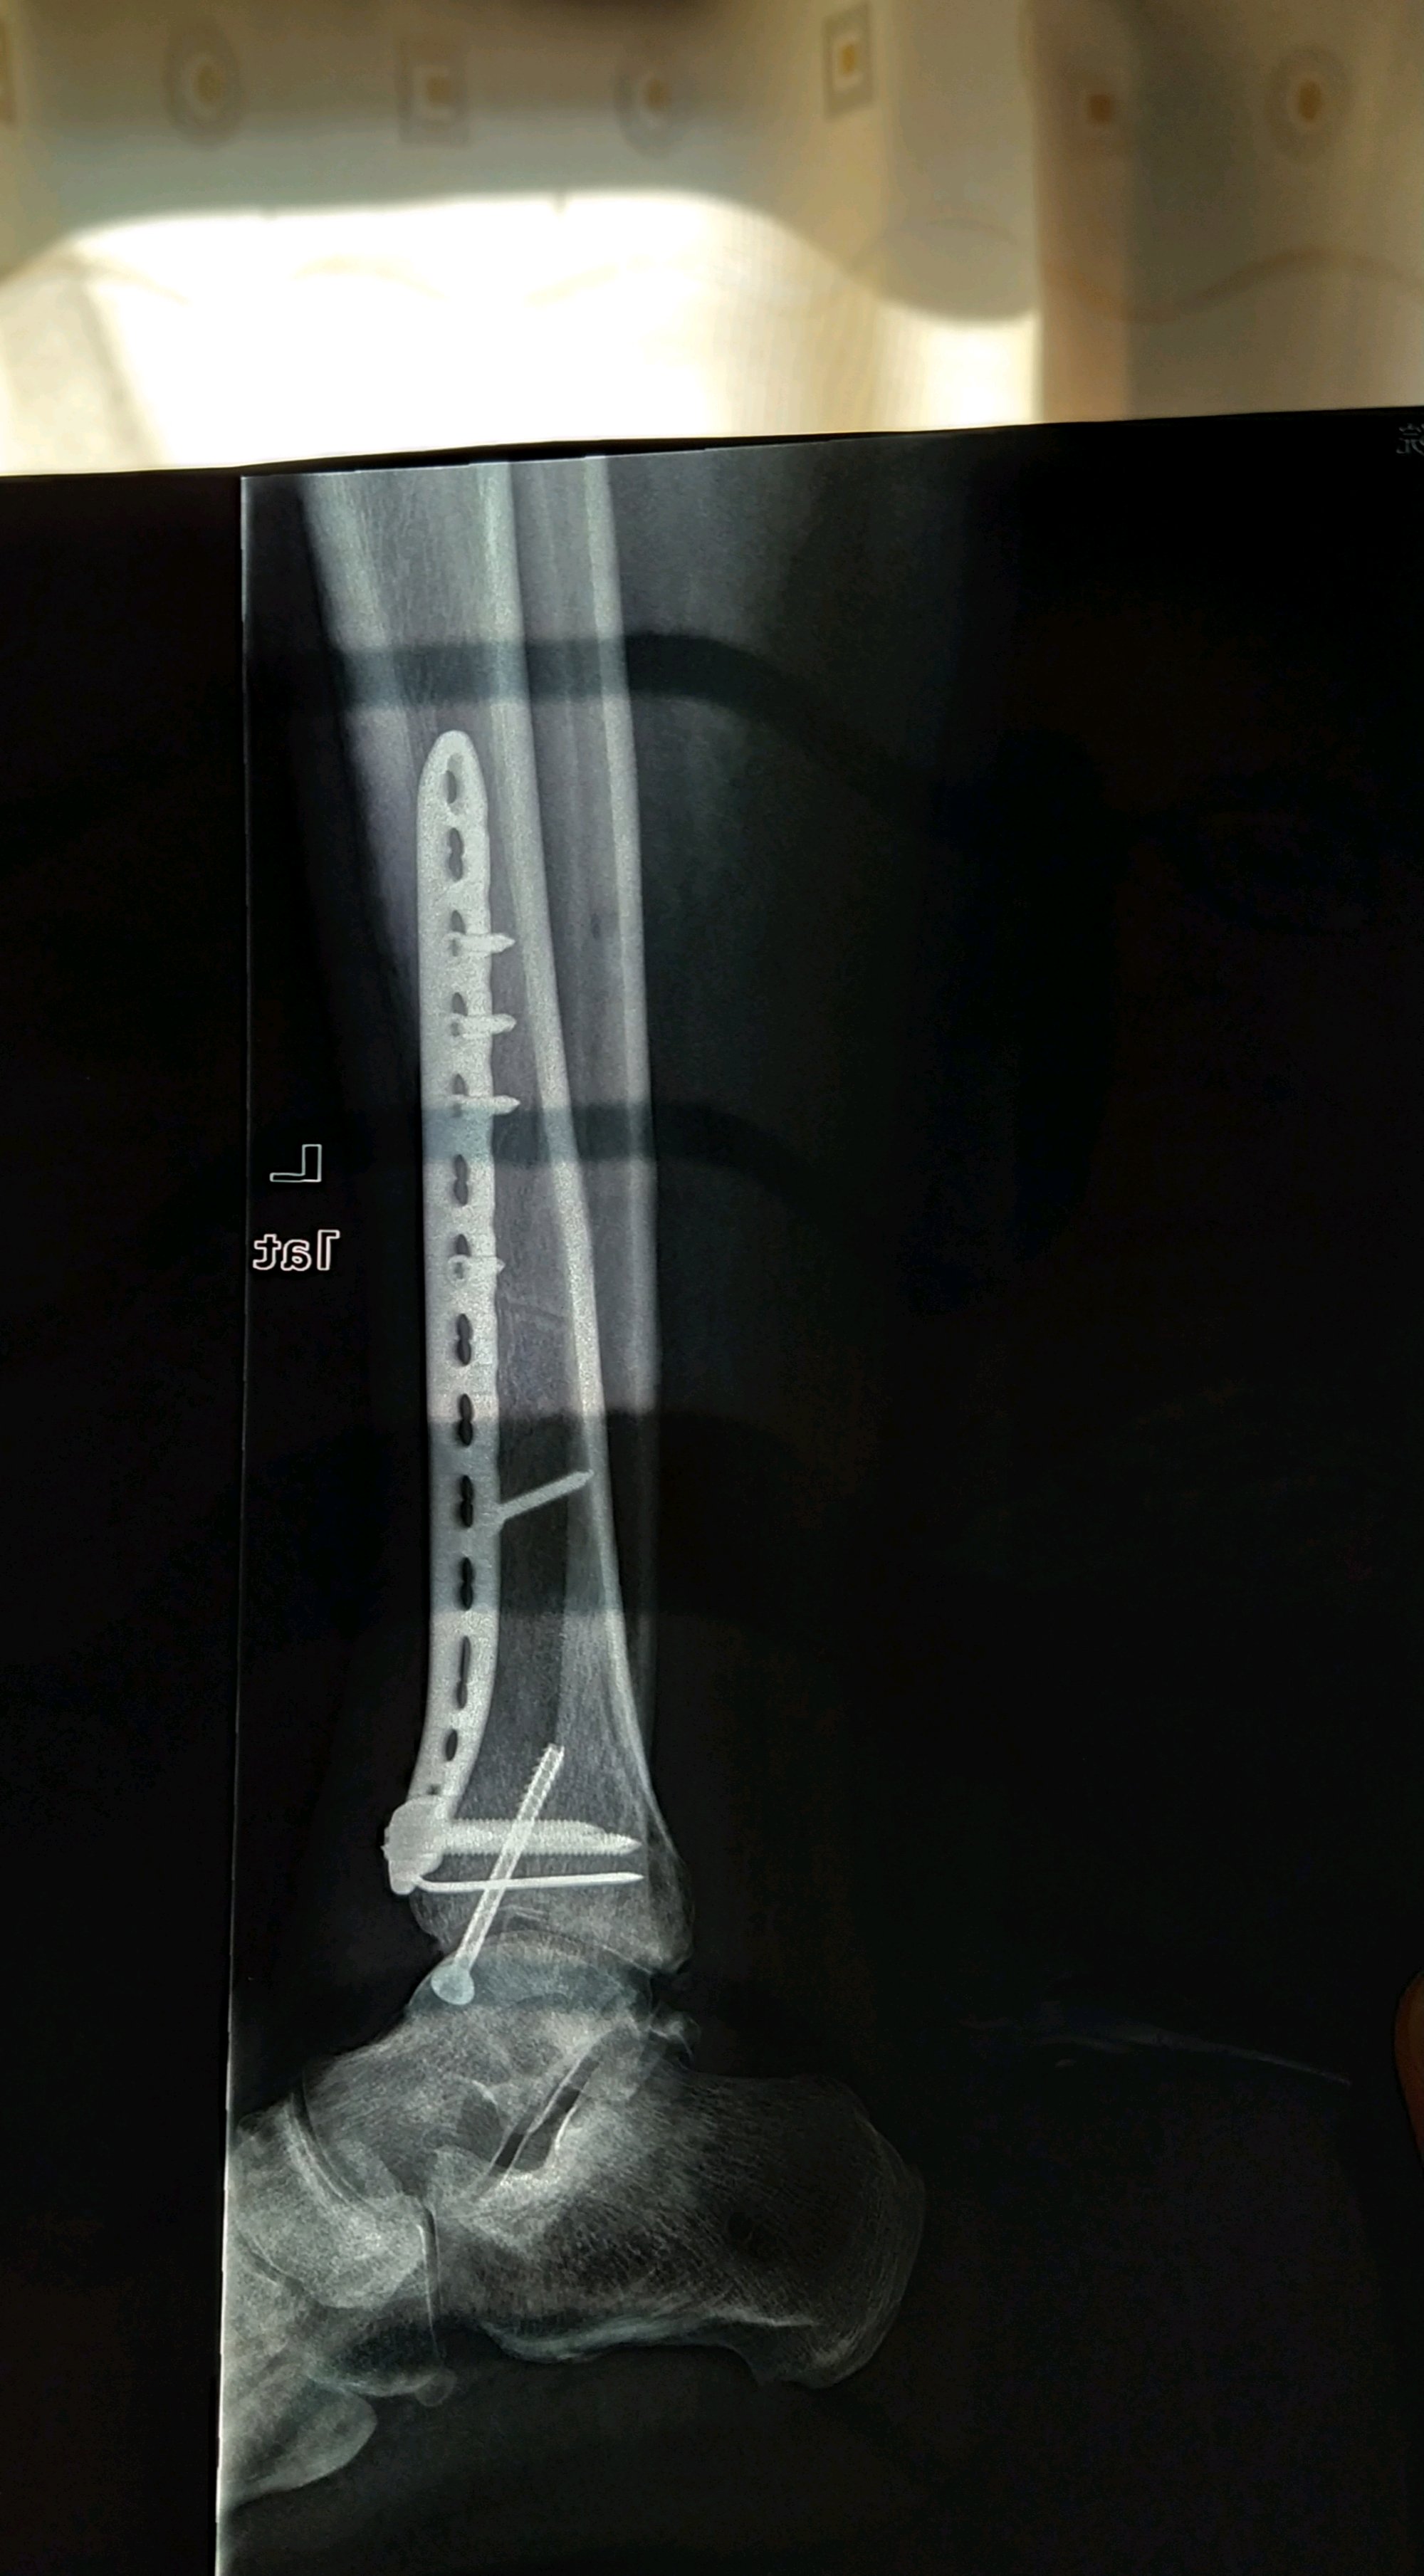

江苏扬州,男,43岁,月薪1w,工伤认定已完成。请问估计能定几级伤残,大概能赔偿多少?